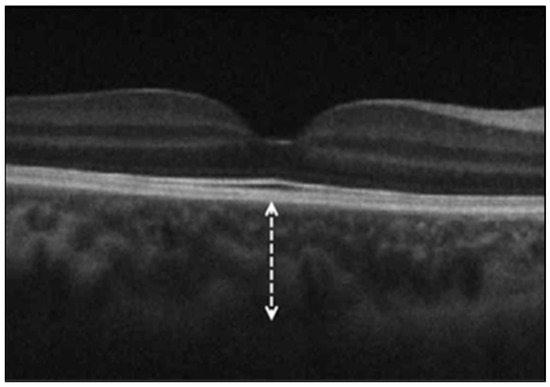

2.2. Optical Coherence Tomography (OCT) Measurements

- Ganglion cell–inner plexiform layer (GC-IPL) thickness, assessed with the Macular Cube 512 × 128 protocol, providing average and sectoral thicknesses.

3.3. Choroidal Thickness (ChT)